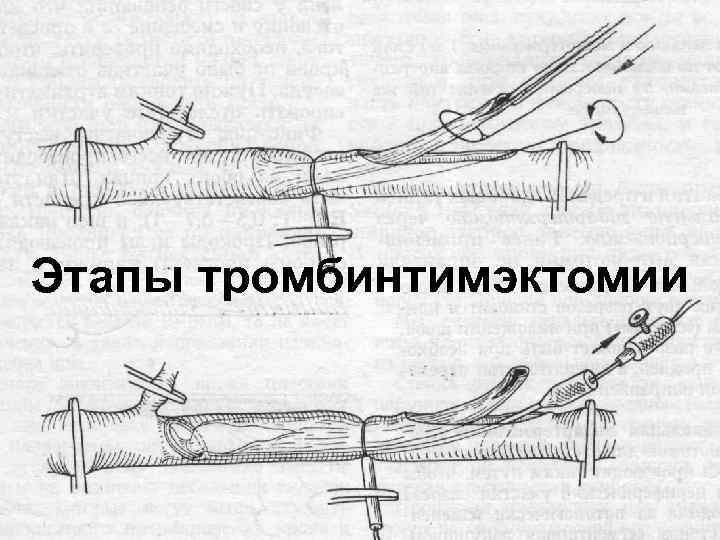

Лечение n При остромбозе показано обследование больного и подготовка его к последующей реконструктивной операции на сосудах. n В наиболее тяжелых случаях и в остром периоде производят тромбинтимэктомию, протезирование сосуда или обходное шунтирование. 29

Этапы тромбинтимэктомии 30